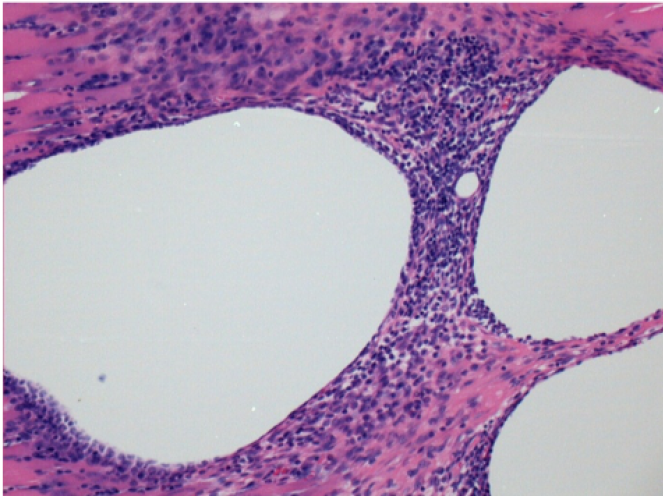

Через 10 днів після ін'єкції Ендопіл 0,1 мл в правий претибіальний м'яз.

Тут можна побачити утворення вакуолей, які оточені лімфоцитами. Вакуолі відрізняються від некрозу тканини. Присутність лімфоцитів пов'язана з проникністю клітинних мембран.

Через 1 місяць після ін'єкції Ендопілу 0,1 мл у правий претибіальний м'яз.

Те, що видно на знімках чорним кольором, не є некрозом, як можуть собі уявити деякі науковці!